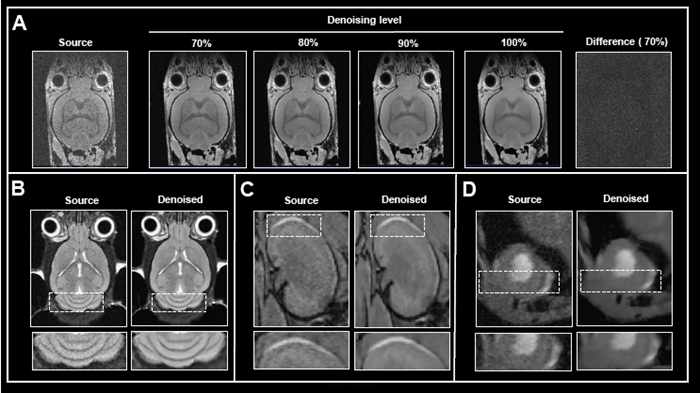

In addition to network options, the denoising level can be selected. Fig 2A shows the effect of applying various levels of denoising to image reconstruction.

Mouse brain data was obtained ex vivo, and the original data was rebuilt without and with increasing denoising levels (70-100%). Increasing the level of denoising produces images with gradually less noise. Importantly, no artifacts were introduced during the procedure.

Computing the difference images between the source and 70% denoised images revealed that only noise was selectively eliminated. If the original signal at the image's edges is reduced due to bandwidth selection, high denoising levels (90 and 100%) can result in a hazy look of edges.

The appropriate denoising level, which balances efficient noise removal with edge blurring, must be determined for each data set or, at the very least, each application protocol.

The effect of image denoising on image quality.

Figure 2. The effect of image denoising on image quality. A) Applying increasing levels of denoising. Shown are axial images of a 3D T1-weighted FLASH ex vivo data of a fixed mouse head acquired at 9.4 Tesla without (Source) and different levels (70-100 %) of denoising. A difference image between the source and 70 % denoised images was computed. B)-D) Comparison of in vivo images reconstructed with no denoising and with 70 % denoising. B) Coronal T2-weighted TurboRARE images of a mouse brain acquired at 3 Tesla. C) Coronal 3D FISP images of mouse kidney acquired at 7 Tesla. D) Short axis view of a mouse heart acquired with a flow-compensated triggered FLASH sequence at 9.4 Tesla. For different data, either no denoising (Source) or denoising using individual networks and a pre-denoising of 50 % was applied (Denoised). Image Credit: Bruker BioSpin Group

The efficacy of Smart Noise Reduction was illustrated using in vivo mouse data from various organs collected at various magnetic field strengths (Fig 2B-D).

Compared to reference images of the brain, kidney, and heart, reconstruction with 70% denoising resulted in images with substantially less noise and a better look of anatomical details and edges.